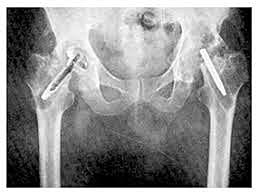

• Bolhlman y Moore

Bolhlman y Moore

sustituyeron la extremidad proximal del fémur por una endoprótesis de vitalio, en un paciente que padecía una degeneración maligna de un tumor de células gigantes

• Moore y Reyman

Moore y Reyman

diseñaron una nueva endoprótesis femoral de vitalio, que se fijaba intramedularmente en la diáfisis sin necesidad de emplear cemento, debido a los grandes orificios que presentaba el vástago, Los hermanos Judet utilizaban un abordaje anterior de Smith-Petersen, mientras que Moore lo hacía por vía posterior